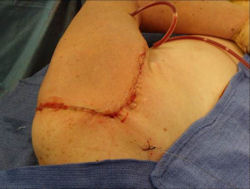

Examples of radical limb sparing surgeries for osteosarcomas in various anatomic locations (distal femur, proximal tibia, proximal humerus, scapula)

In each case, the tumor and bone from which it arose were resected. This required meticulous dissection, mobilization and preservation of adjacent pertinent neurovascular structures. In each case presented here, the defect was reconstructed with a special modular segmental tumor prosthesis. This also replaces the adjacent joint in many instances.

Proximal Humerus: Radical Limb Sparing Extra-Articular Resection and Prosethetic Reconstruction